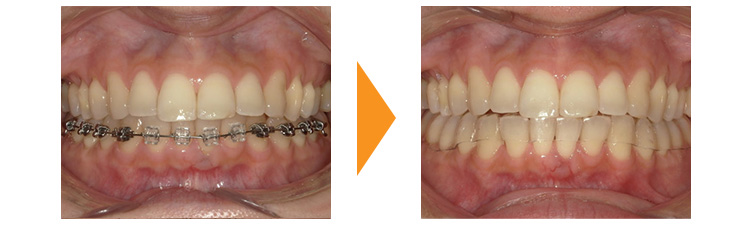

子供の時に矯正治療を行っていた患者様です。矯正後は並んでいたが、矯正治療後2年経過した段階で保定装置(リテーナー)を除去し、親知らずをぬいていなかったため前歯のガタガタが戻ってしまったとのことでした。

幸い奥歯の噛み合わせなどには問題なかったため、下顎のみの部分的な矯正治療で対応できました。

親知らずの存在と保定装置を撤去したことが後戻りの原因であるため、矯正中に親知らずを抜歯していただき、保定装置は取り外しのできない舌側固定は半永久的に使用し、取り外し式のマウスピースも夜間は必ずしていただく必要があることを事前に説明し矯正治療を行いました。

矯正治療は並べて終わりではありません。矯正後は保定・維持の始まりでもあります。歯並びによっては保定装置の使用が必要ない場合もありますが、基本的には長期間の保定装置の使用が望ましいことをよくご理解いただけたらと思います。

| 初診時 | 36歳女性 |

|---|---|

| 主訴 | 後戻り後の下前歯のガタガタ改善希望 |

| 期間 | 約9か月 |

| 矯正 | 部分矯正・ブラケット・ワイヤー |

| 費用 | 基本検査22,000円・契約料220,000円・調整料5,500円/月(税込) |

| 治療上のリスク | 歯磨き不良の場合はむし歯になる可能性。 習癖に伴う後戻りの可能性。 |